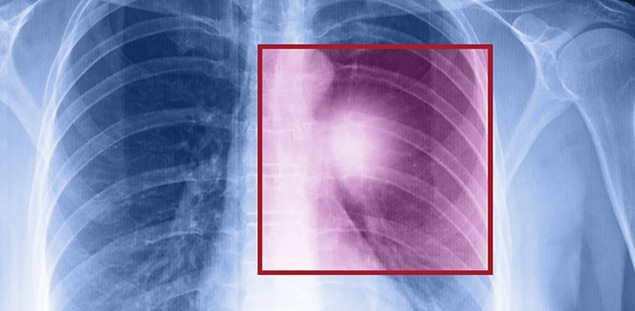

Akciğer Kanserinin En Sinsi 9 Bulgusu..

Kanser tanısı bu biyopsi örneğinin patolojik incelemesi sonucunda kesinleşiyor. Kanser tanısının konmasının ardından hastalığın yaygınlığının tespitinde PET/CT gibi yöntemler kullanılabiliyor.